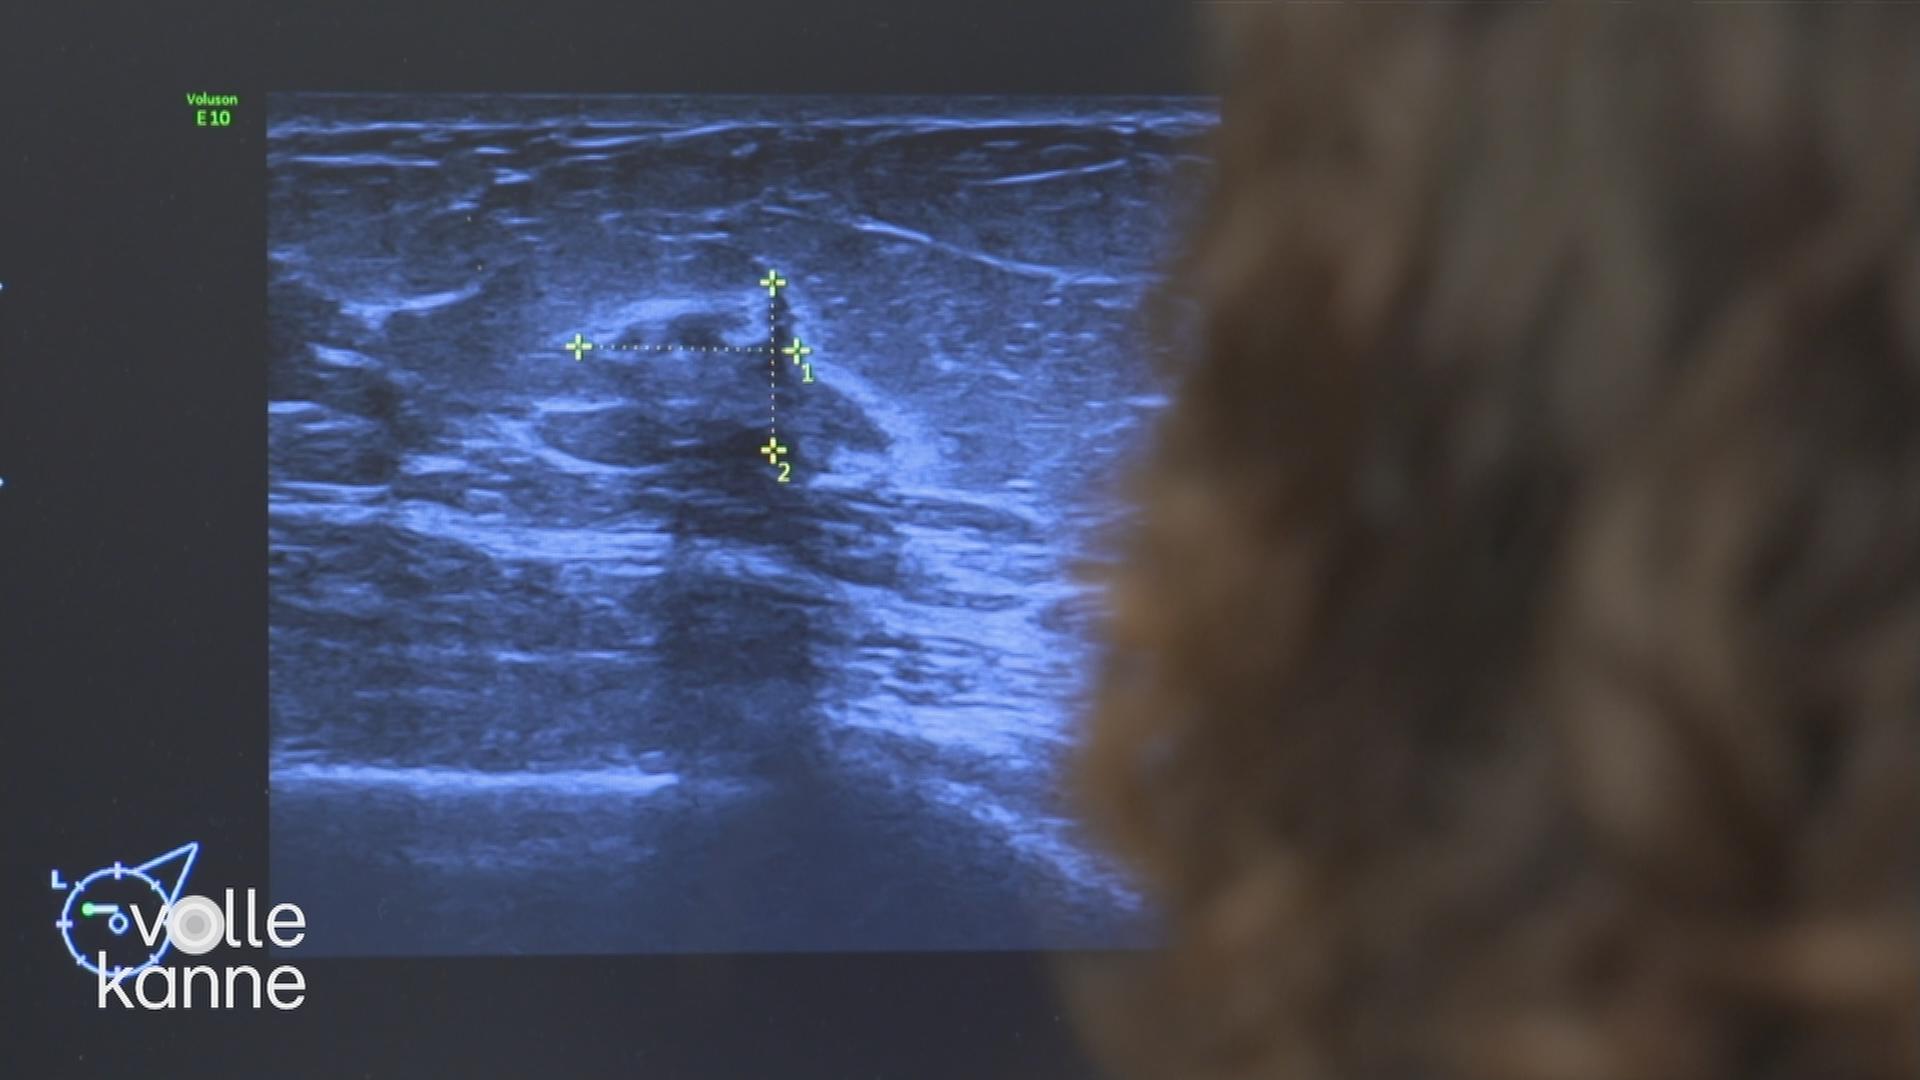

Bei Knoten und Schmerzen in der Brust denken viele Frauen sofort an Krebs. Aber es könnte auch nur eine Mastopathie sein – eine gutartige Erkrankung der weiblichen Brust, bei der sich das Brustgewebe verändert.